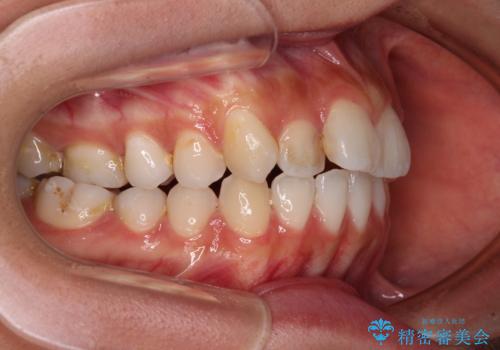

- 前歯のデコボコと口元の突出感を気にして来院された患者様です。

口元の突出感が認められ、更には左右で異なる咬合状態であったため、下顎右側は第二小臼歯を、左側は第一小臼歯を抜去することでバランスを取るような治療計画としました。